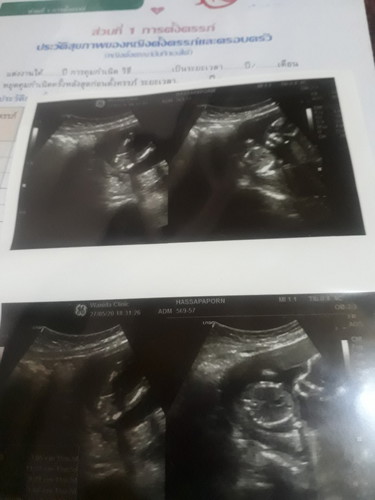

บ้านนี้คลอดเดือน 1พ.ย หมดบอกตัวใหญ่มาก เป็นผู้ชายบ้านนี้ชาย2คนเลยครับแม่อยากได้ ผู้หญิงแต่ผู้ชายอีก?????